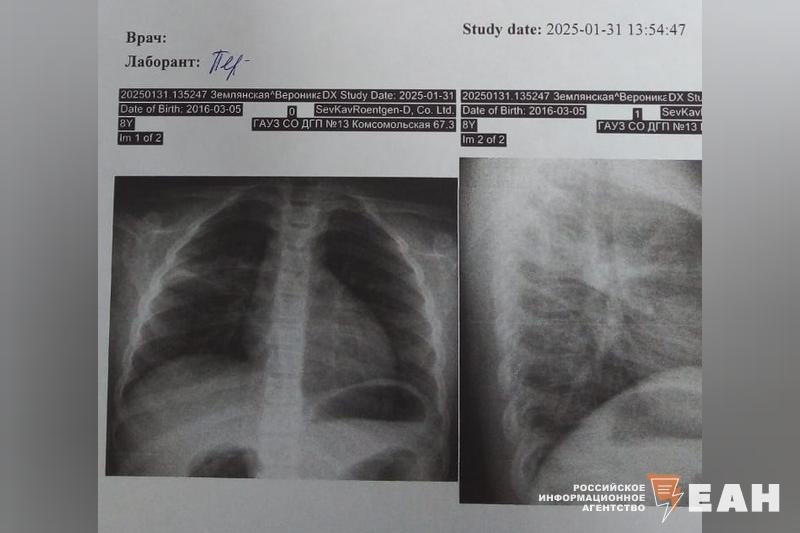

Казалось бы, обычно на второй-третий день после приема антибиотиков состояние значительно улучшается. Но в этот раз что-то пошло не так, и температура продолжала подниматься до 39 градусов. В пятницу был назначен прием в поликлинике, на котором я настойчиво попросила направить нас на рентген легких. В этот раз нас наконец-то направили на анализ крови и дали направление на рентген. Вечером попросили прийти к врачу в неотложке, чтобы узнать результат и при необходимости скорректировать лечение. Рентген показал правостороннюю верхнедолевую пневмонию.

В неотложку я уже пошла без Ники, чтобы ее не тащить в поликлинику четвертый раз подряд. Увидев снимок, врач беспрекословно сказал, что необходима госпитализация, и начал пугать, чем опасно лечение дома.